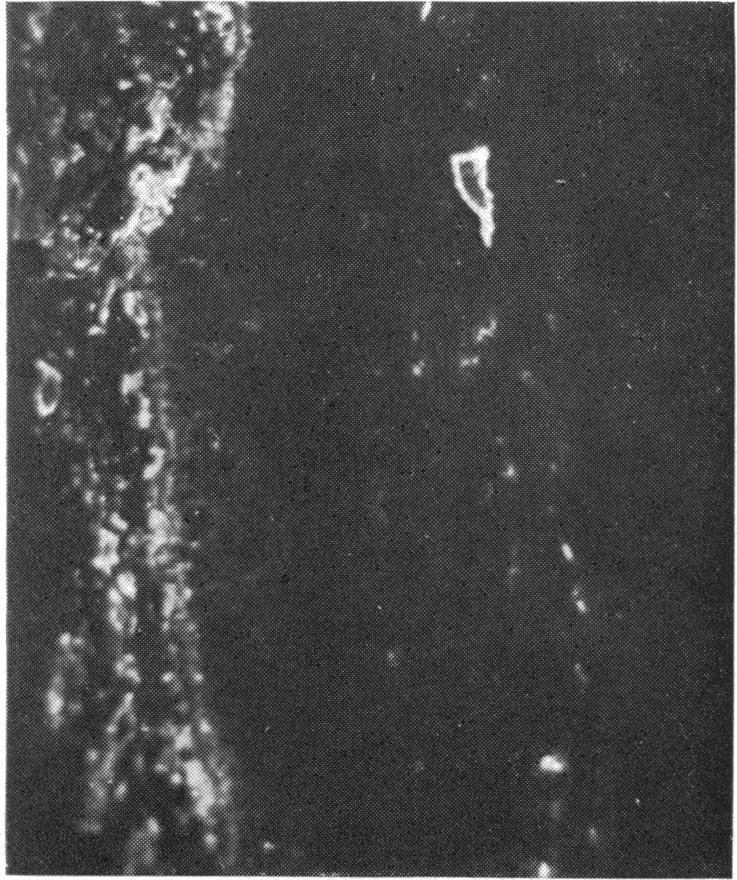

Reticulum fibres in relation to retinal vessels.

Argyrophilic perivascular and intervascular fibres in the mammalian retina are shown by specific antireticulin immunofluorescence to consist of reticulin. The possible significance of these findings is briefly discussed.